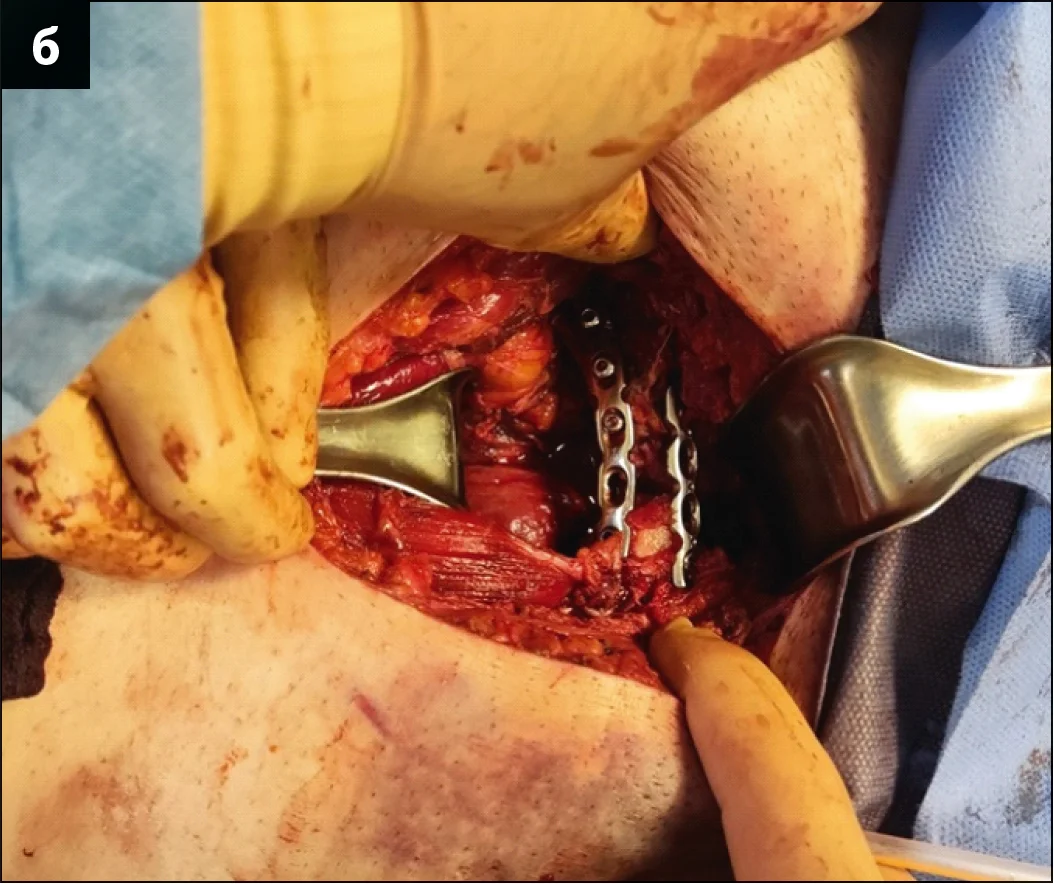

За допомогою наступного оперативного прийому виконувалася провізорна репозиція та фіксація двох півкілець таза шляхом заведення гвинтів, фіксації проволокою та репозиційними щипцями. Сечовий міхур за таких втручань відводиться мануально серветкою, щоб запобігти інтерпозиції останнього між лобковими кістками. Фіксацію переднього півкільця таза виконували пластиною, що розташовувалася по верхньому краю лобкових кісток. Враховуючи значне первинне порушення цілісності тазового кільця, додатково лобковий симфіз фіксували реконструктивною пластиною з чотирма отворами для кращої міцності (рис. 4). Фіксацію заднього півкільця таза, а саме клубово-крижового з’єднання, проводили закрито під рентгенологічним контролем канюльованим гвинтом через клубову кістку в напрямку тіла 1 крижового хребця (рис. 5).

Рис. 4. Інтраопераційна візуалізація оперативного прийому з фіксації лобкового симфізу: а – провізорна фіксація двох півкілець таза (білою лінією позначено контури лобкових кісток); б – остаточна хірургічна фіксація переднього півкільця таза пластинами